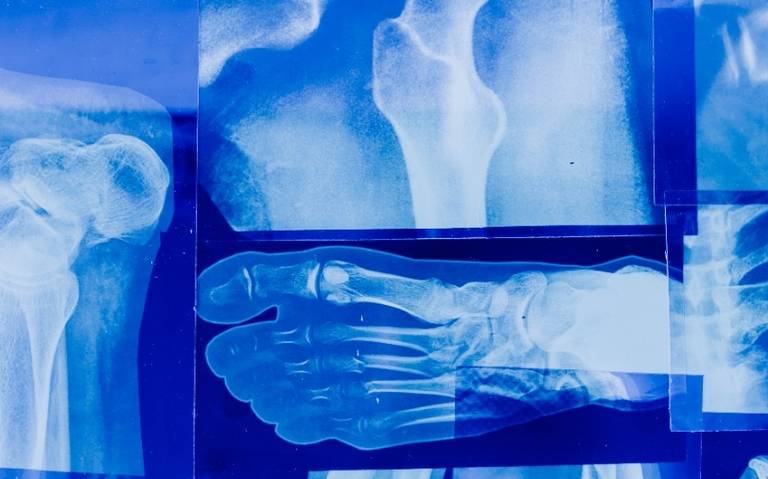

La mala calidad ósea aumenta la fragilidad, riesgo de fracturas y de osteoporosis

El médico agregó que poer esta razón es importante practicarse una densitometría ósea, estudio que paraermina la densidad y calidad de los huesos, para poder brindar a la persona un tratamiento.

Añadió que la osteoporosis es una enfermedad crónica y progresiva que origina una disminución de la masa ósea, con el aumento de su fragilidad y fracturas.